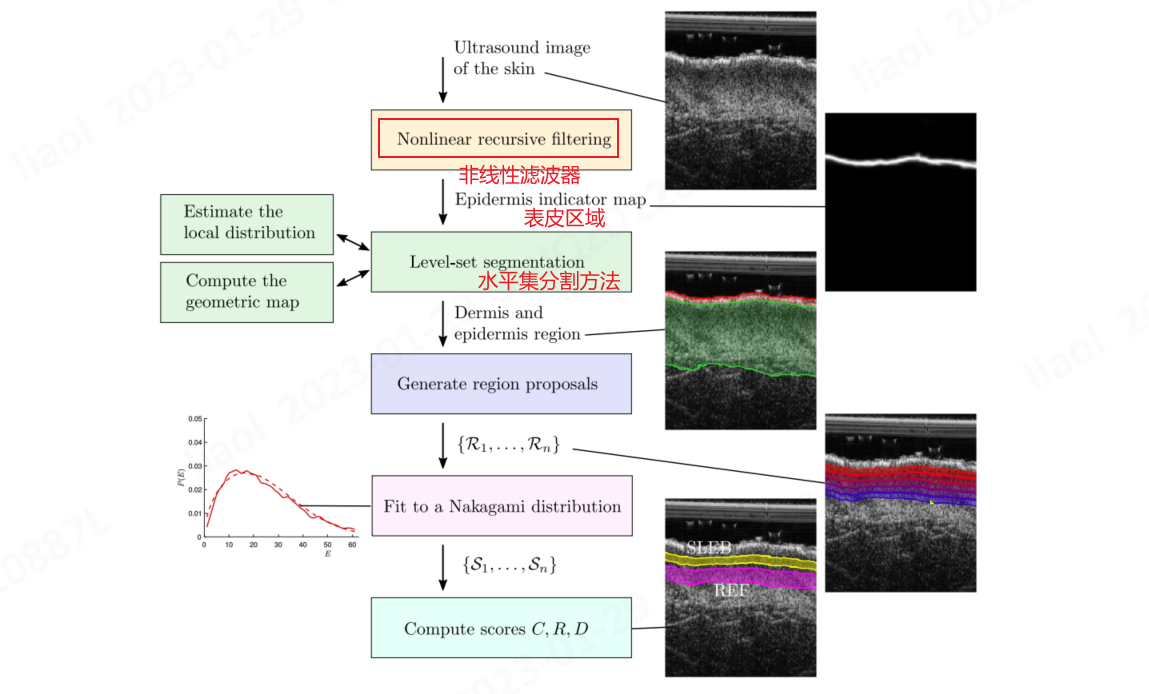

提出了一种具有非线性滤波器的递归方法来自动检测表皮,改进水平集的方法自动检测真皮层;

真皮层分割

一种多重损失水平集分割算法,结合纹理准则、表皮mask和水平连续性的几何约束,将表皮和真皮层联合分割(Proposed)。